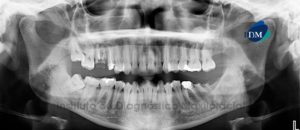

Paciente femenino, de 73 años de edad es referido al Instituto de Diagnóstico Maxilofacial (IDM) por motivos prostodónticos. La paciente es edéntula parcial bimaxilar la